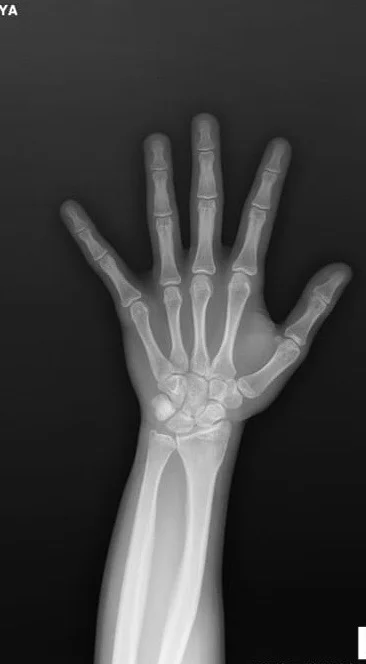

Epifiz plağım kapalımı ?

Bilen kişi varsa yardımcı olabilirmi.

kapalı. ameliyat harici uzamanız mümkün değil. kas uzamasından kaynaklı barfiks ile beelki 1-2cm elde edebilirsiniz.

kapanmışsa bir şey yapılamaz ama yaş kaç hocam?